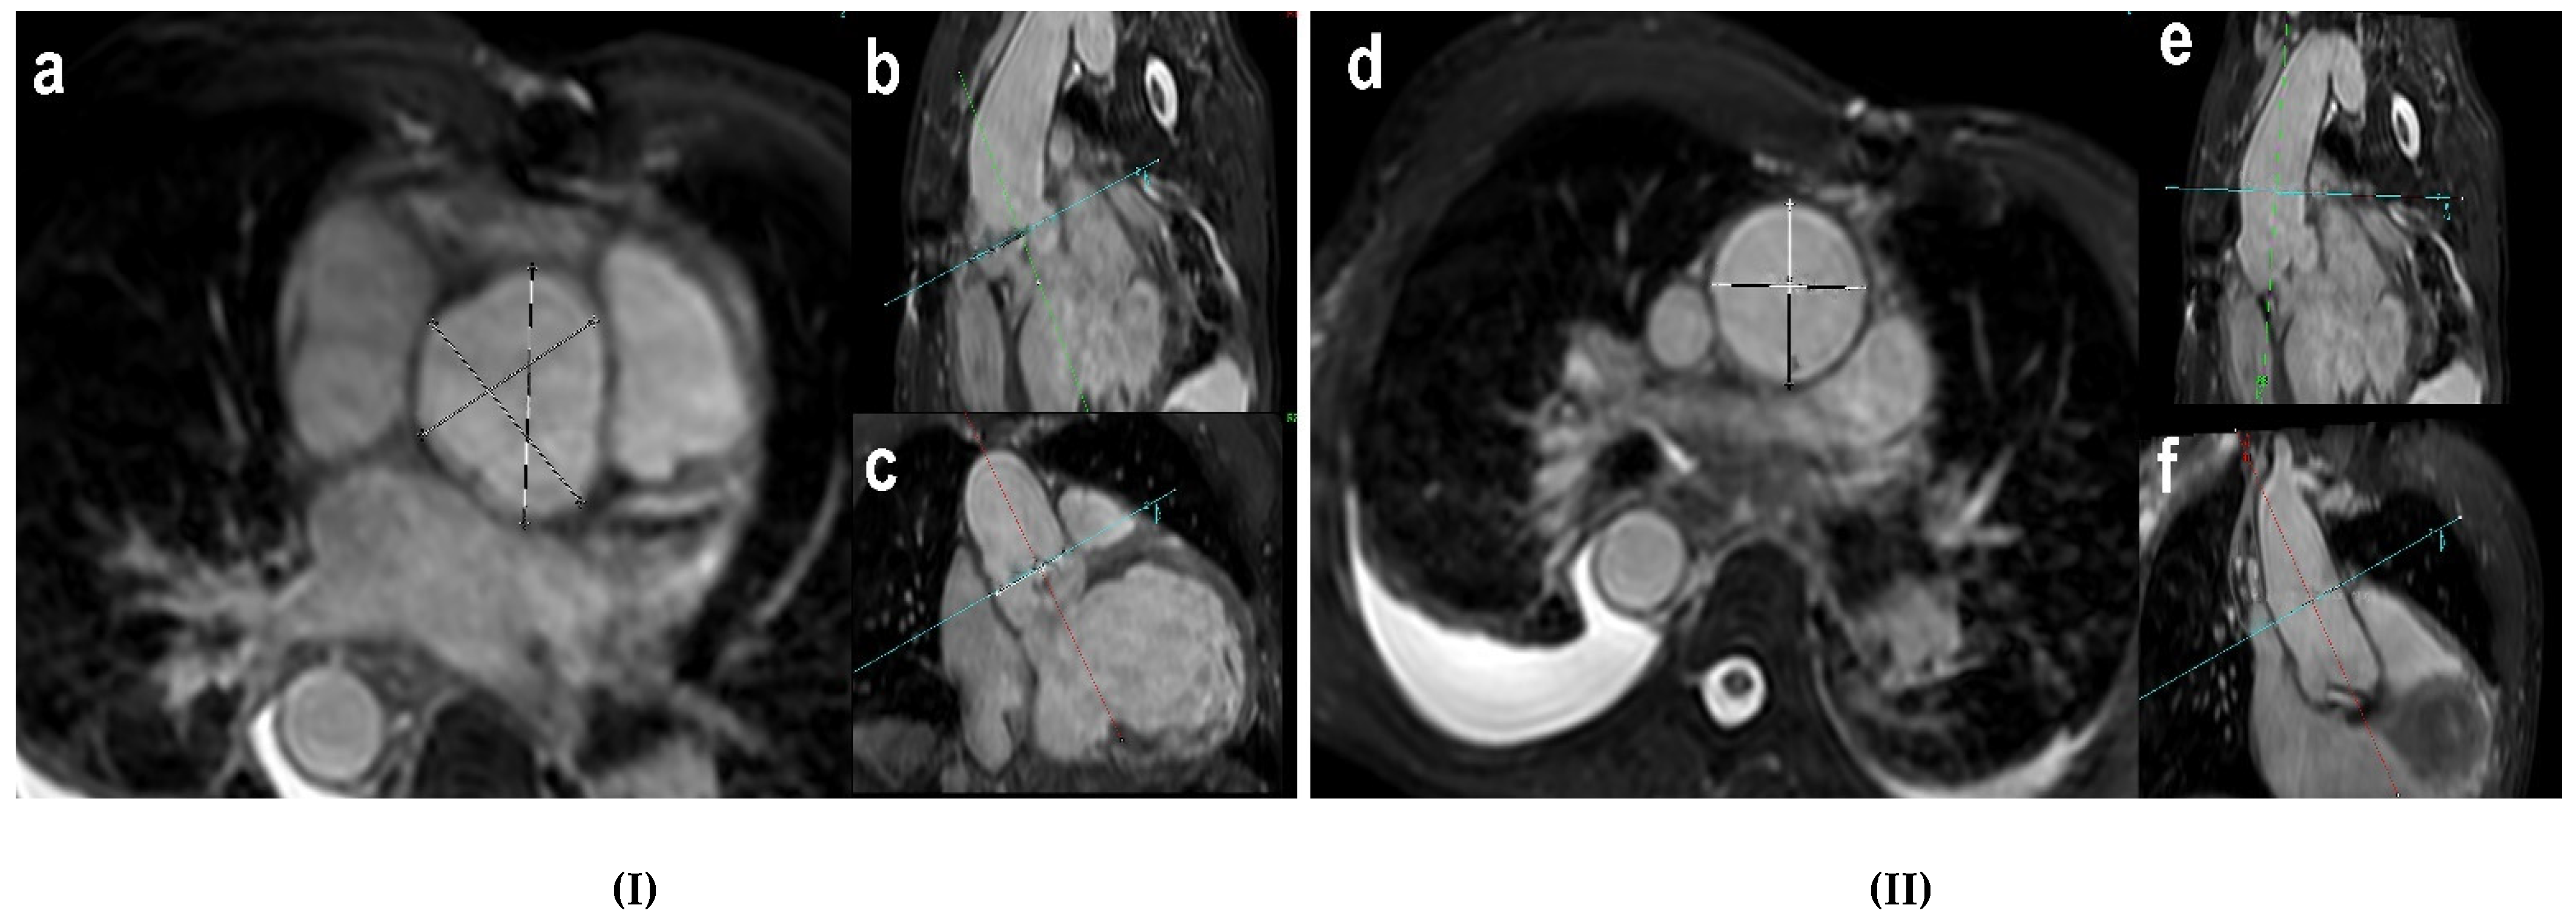

2.3. Cardiac Magnetic Resonance Imaging